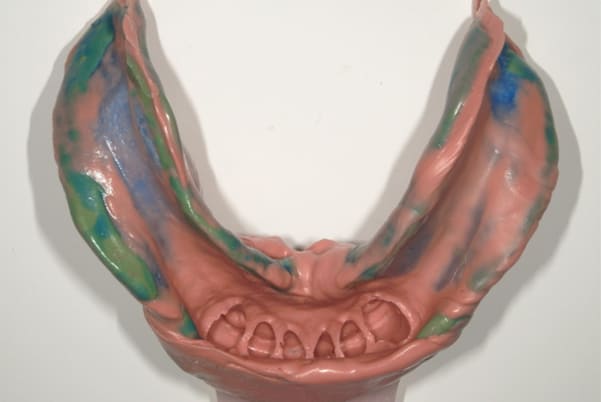

下顎治療前

-

下顎治療後

治療前の入れ歯の奥歯は、治療後の義歯と比較しても分かるように、歯が削れ平らになった状態です。

これにより奥歯のかみ合わせは低くなり、前歯のみが強くあたり、かみ合わせにより上の前歯大きな負担がかかっていたことにより、上の前歯が折れたことが考えられます。

精密な型どり

精密な型どりは、通常保険治療では使用しない、この患者様だけに合った型を取るトレーを作製、また寸法変化の最も少ない精密なシリコンを用いてお口の中を精密に限りなく再現する型どりの方法で型をお取りしました。